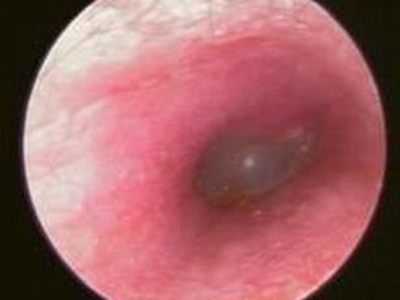

外耳道炎外耳道里有白色粉末状物图

外耳道炎在外耳道表现为侧壁水肿发红,上附有一层白色粉末状的鳞屑,薄厚不一,患者出现耳内疼痛、耳道肿胀的表现,严重者伴有听力下降。